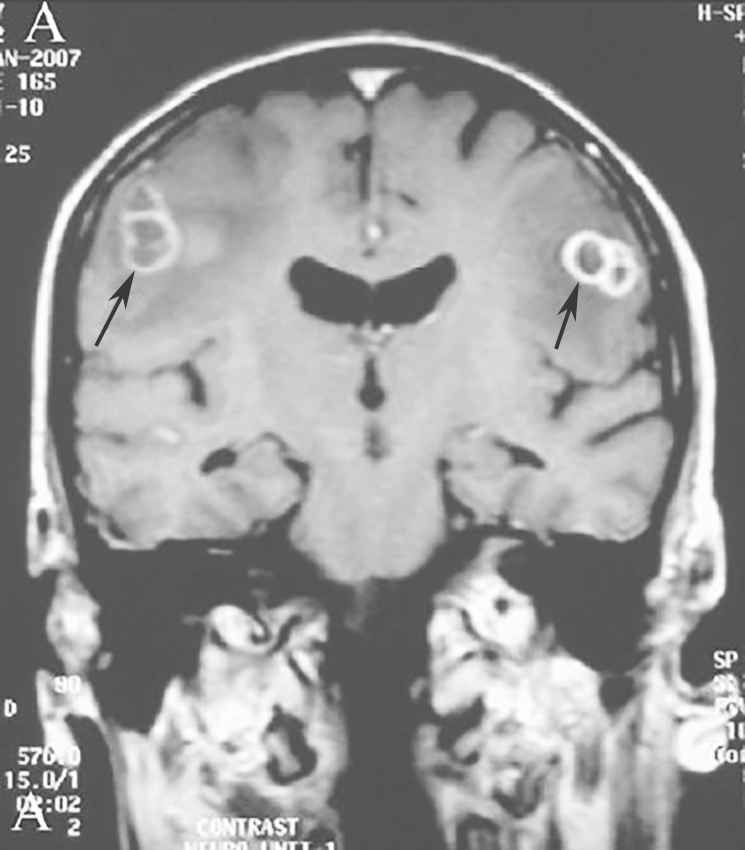

从患者的胸部影像学表现来看,需要警惕血行播散性诺卡菌感染的可能,而这类病变容易合并颅内病变,遂急行头颅MRI,显示颅内多发环形病变(图6),考虑为合并颅内感染。

图6|头颅增强MRI

增强MRI示颅内多发环形增强的占位性病变,周围水肿明显